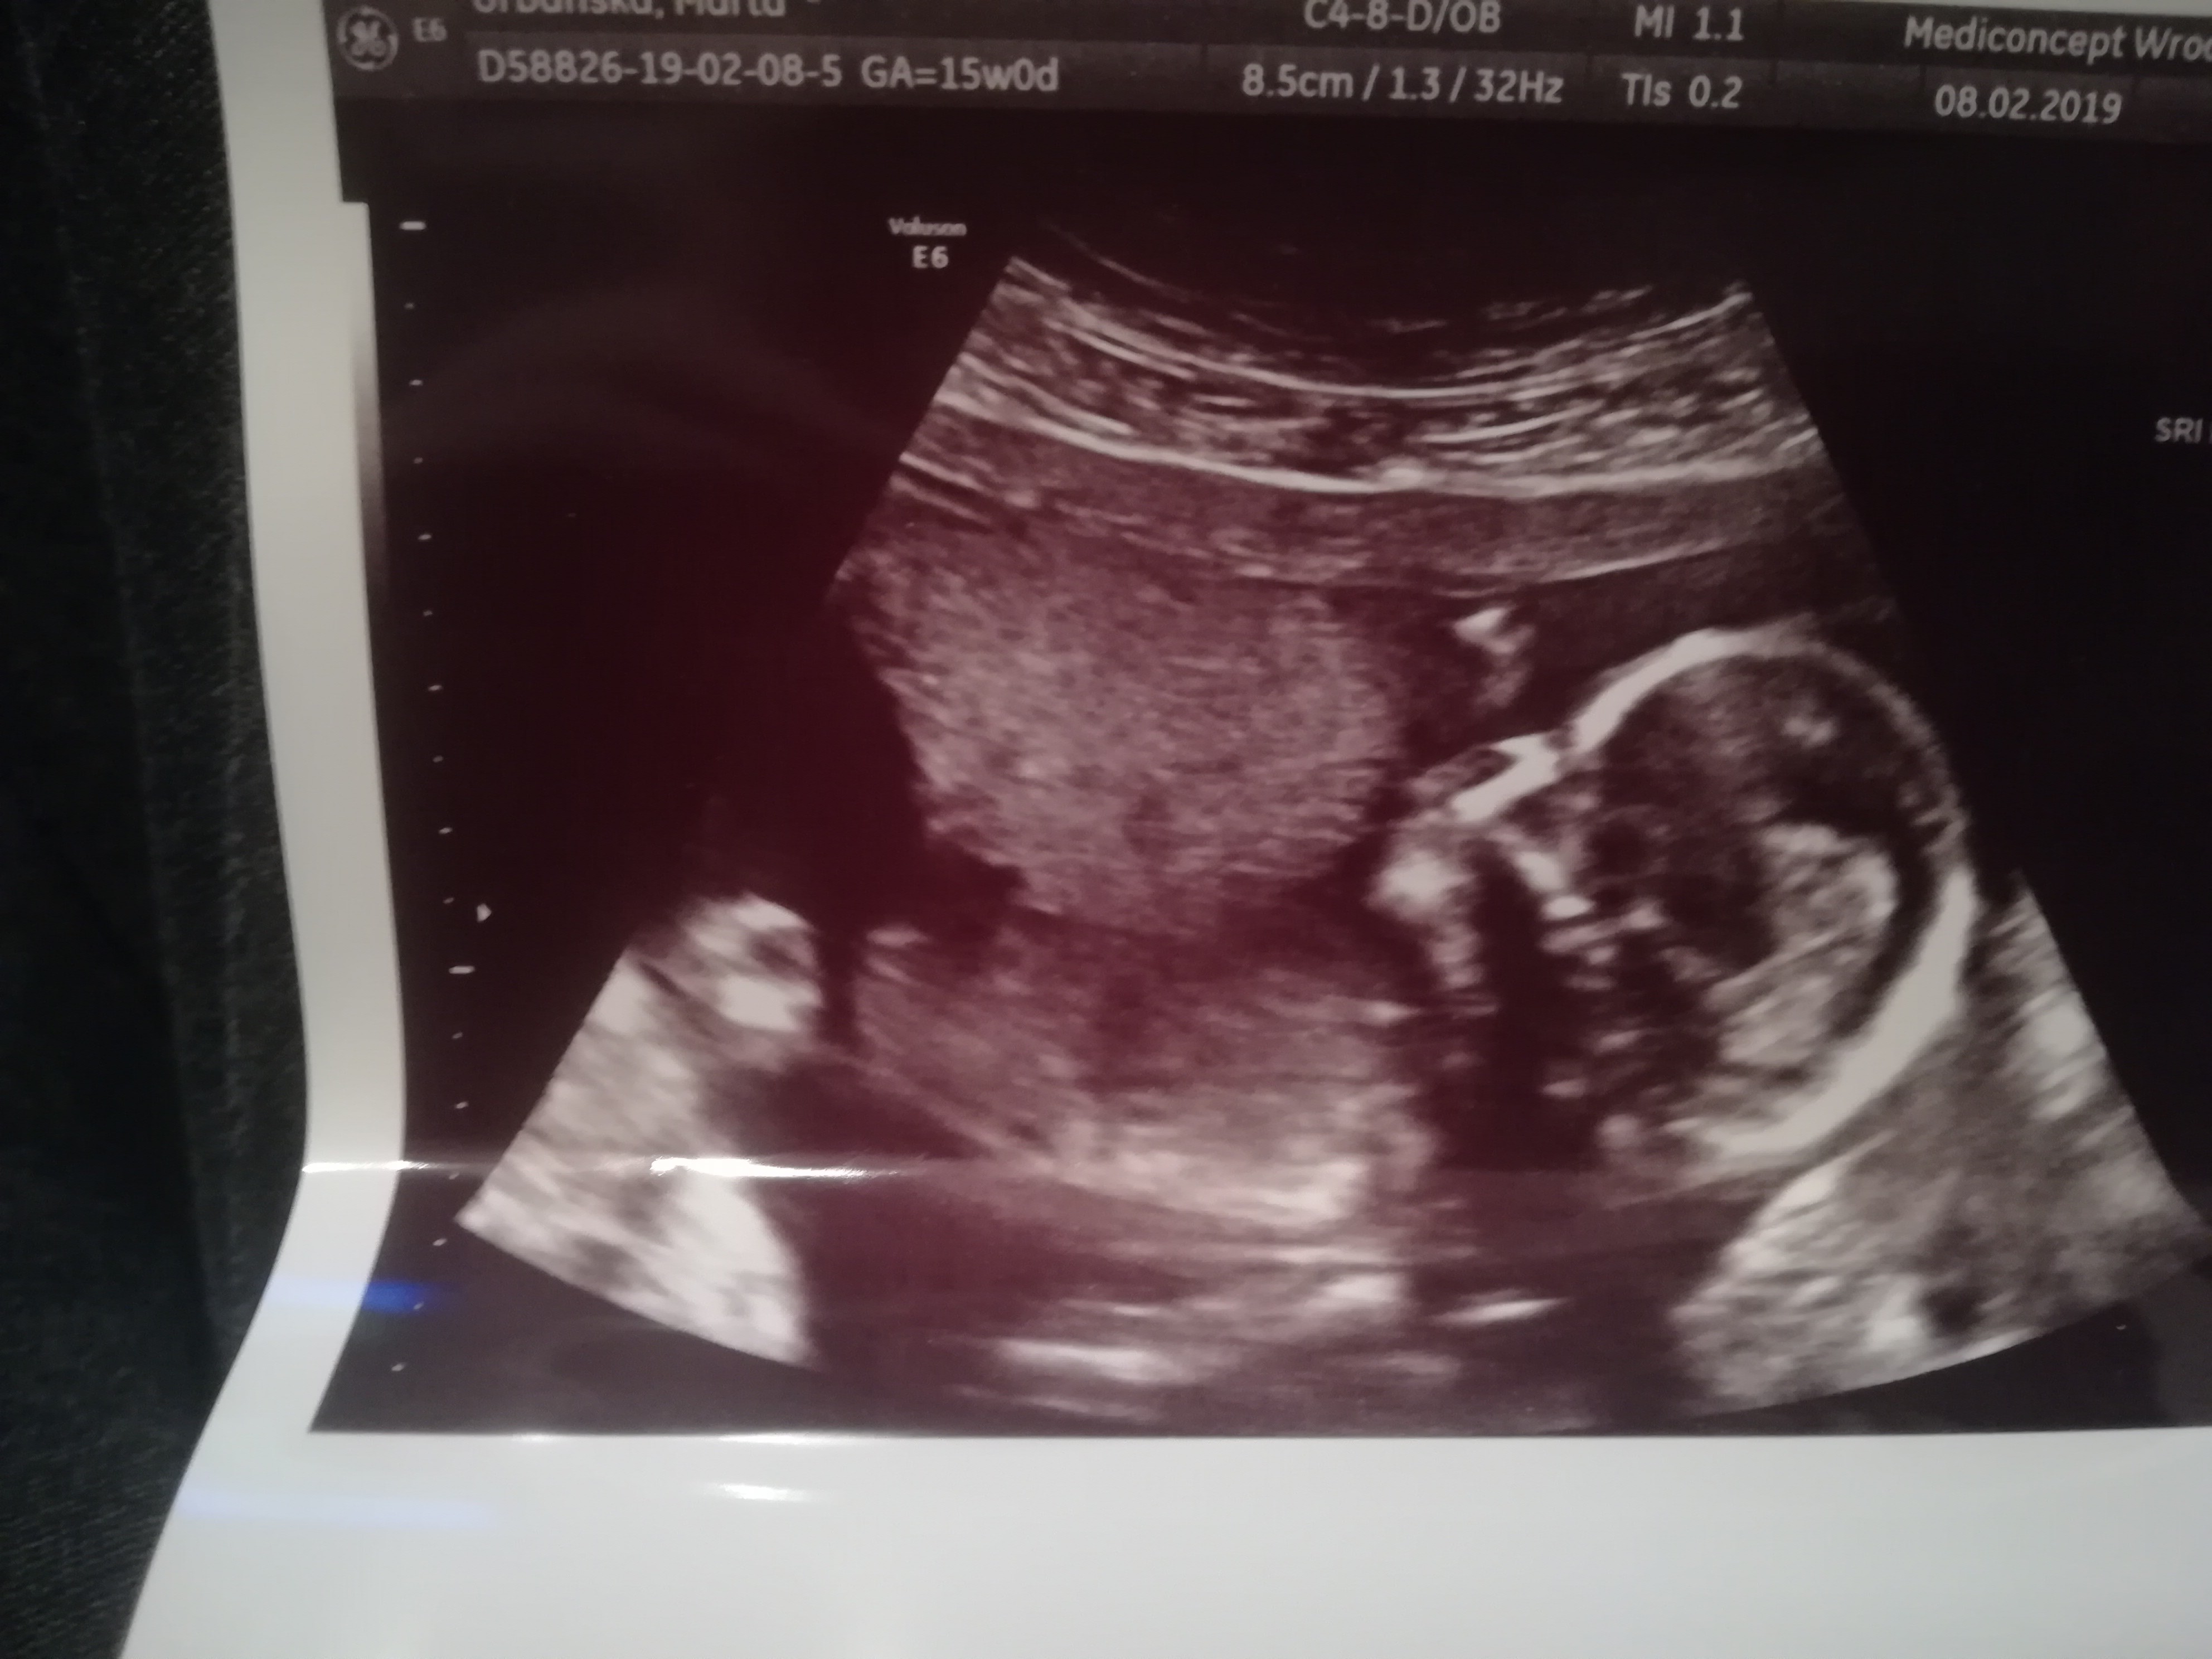

Dziewczyny melduję się po wizycie 1,5 godz opóźnienia

Dzidziolek zdrowo rośnie serducho bije wszystko ok i na 80% dziewczynka

• IMG_20190208_200739.jpg

IMG_20190208_200739.jpg

1 022,2 KB · Wyświetleń: 92